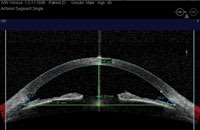

OCT of nasal and temporal sections of the anterior chamber angle including dimensions of key structures. |

Recent technological advances for glaucoma management include ocular coherence tomography (OCT) available for the anterior segment of the eye. Examples of this include Visante (Carl Zeiss Meditec) and SL OCT (Heidelberg Engineering). In addition, Portable Ophthalmic Devices is seeking FDA-approval for an ultrasonic device that is presently used for small-animal research and veterinary ophthalmic diagnosis. This device provides dynamic images of anterior segment. For instance, we can visualize changes in the configuration of the anterior chamber angle, iris, lens and ciliary body in the light and dark. This can add important information in the work-up of a glaucoma patient with a suspected narrow angle component.

The Stratus OCT (Carl Zeiss Meditec), used clinically for the evaluation of the retina, employs a 0.8 nm wavelength that cannot penetrate the sclera. As such, it is not ideal for assessing the anterior segment. However, the anterior segment version, the SL OCT, uses a longer wavelength that produces clinically useful results. Preliminary clinical studies suggest that anterior segment OCT compares favorably with conventional gonioscopy in its ability to identify potentially occludable angles.

The SL OCT allows for precise evaluation, measurement and analysis of the anterior segment, including anterior chamber depth (ACD), anterior chamber angles and the angle-to-angle distance (anterior chamber diameter). It can also assist in postoperative evaluation because it allows imaging and measurement of intraocular lenses and ocular implants.

The procedure is relatively fast. Additionally, you can perform it in complete darkness as well as in brightly lit surroundings (to assist in the dynamic assessment of the angle). The images are also digitally documented, so you can magnify, enhance, transmit and measure them. In addition, a technician can take the image, freeing the doctor to focus time on assessing the results. Compared with existing technology (ultrasound biomicroscopy), the anterior segment OCT does not contact the eye and provides a higher resolution image.